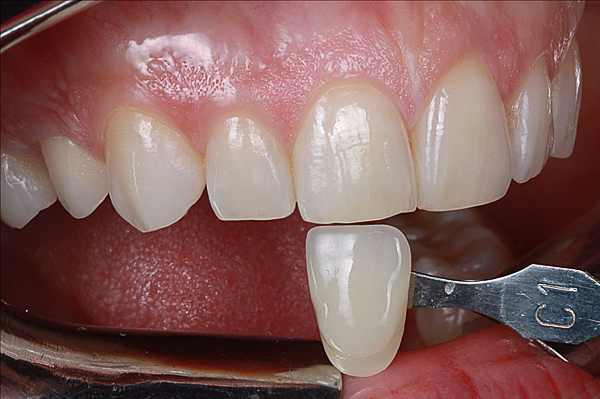

A seguito dell'analisi radiografica viene pianificata l'estrazione atraumatica del premolare con l'inserimento contestuale di un impianto Shelta. La riabilitazione immediata viene eseguita con un pilastro XA per protesi avvitata, su cui viene fissato un provvisorio realizzato in laboratorio secondo i principi dei profili di emergenza della tecnica B.O.P.T.